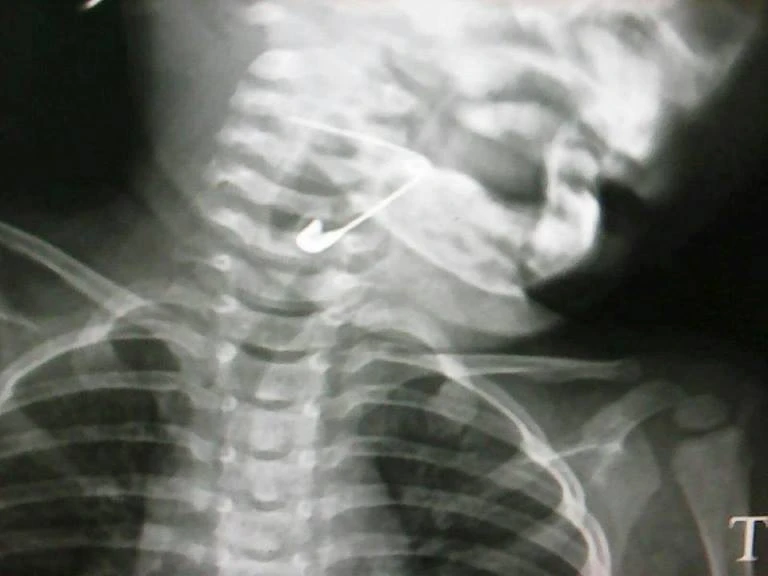

Cây kim băng trong thực quản đứa bé được các bác sĩ phát hiện và gắp ra được. Ảnh: BVCC

Cháu bé nói trên được đưa đến bệnh viện trong tình trạng khó thở, buồn nôn. Ngay sau khi tiếp nhận bệnh nhi, các bác sĩ của BV tiến hành nội soi và phát hiện dị vật ở bên trong thực quản cháu bé.

Sau nội soi, bác sĩ của BV đã tiến hành gắp cây kim băng ra một cách thận trọng. Hiện sức khỏe cháu bé đã được ổn định, chuẩn bị xuất viện.